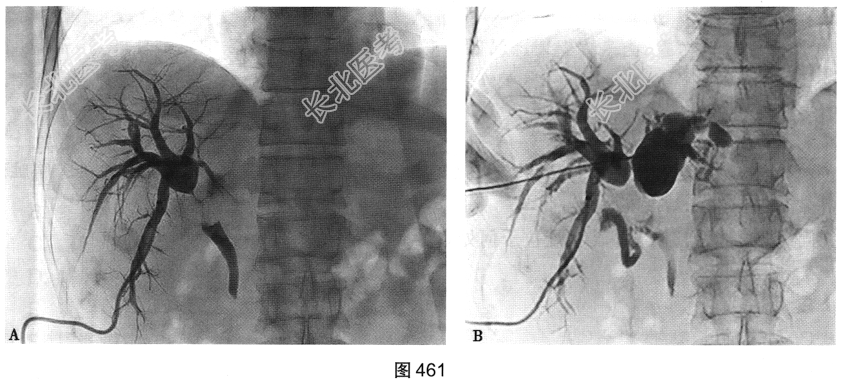

- 多项选择题5.[提示]为了进一步了解患者病变情况,行胆管造影如图461所示。结合上述MRI图像, 按病变累及范围分型,患者属于肝门胆管癌的哪种类型( )

A、Ⅴ型

B、Ⅲb型

C、Ⅱ型

D、Ⅲa型

E、Ⅳ型

F、Ⅰ型